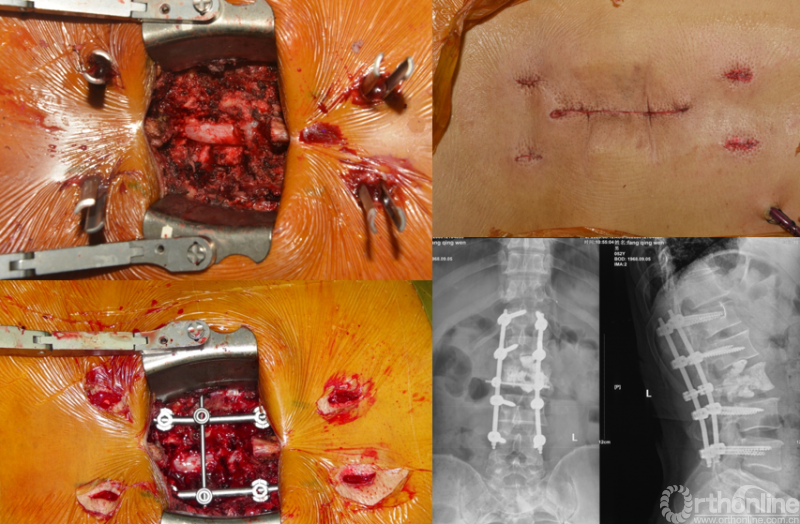

病例详解

患者房某,男性、51岁。主因“腰痛3个月”入院,既往外院诊断“周围型肺腺癌”,全身检查提示多发骨转移。

经Spine Oncology Study Group(SOSG)评估硬膜外脊髓压迫(ESCC)为Grade 1a型,轻度脊髓压迫;脊柱机械稳定性评估(SINS)7分,中度不稳。修正Tokuhashi评分(RTS)6分,预计生存<6个月,建议姑息性手术及保守治疗;结合Tomita评分系统6分,故行姑息性手术短期控制。

影像学资料

PVP治疗

术后6个月

患者腰椎转移瘤术后9个月,因“腰痛伴右下肢疼痛麻木2个月”再次入院。既往在PVP术后曾行化疗及服用埃克替尼靶向药物维持治疗,查体一般状况良好,自主行走,右大腿前外侧麻木。

入院影像学资料

经脊柱转移瘤专业评估,ESCC分级为Grade2,对放疗不敏感;SINS评分8分,中度不稳。Karnofsky功能状态评分90%,预计生存时间6个月。NOMS流程建议分离手术和SRS。

常规分离手术可进行360°脊髓减压,充分固定恢复脊柱稳定;但由于其暴露范围广泛,创伤较大,并不适宜患者当前治疗。

为进一步减少创伤,获得更好的综合疗效。骨采用经皮内固定的微创杂交技术,暨经皮内固定结合小切口分离手术,手术失血900ml,术后7天出院。

术中资料

手术视频:http://res.orthonline.com.cn/video/SSZH.mp4